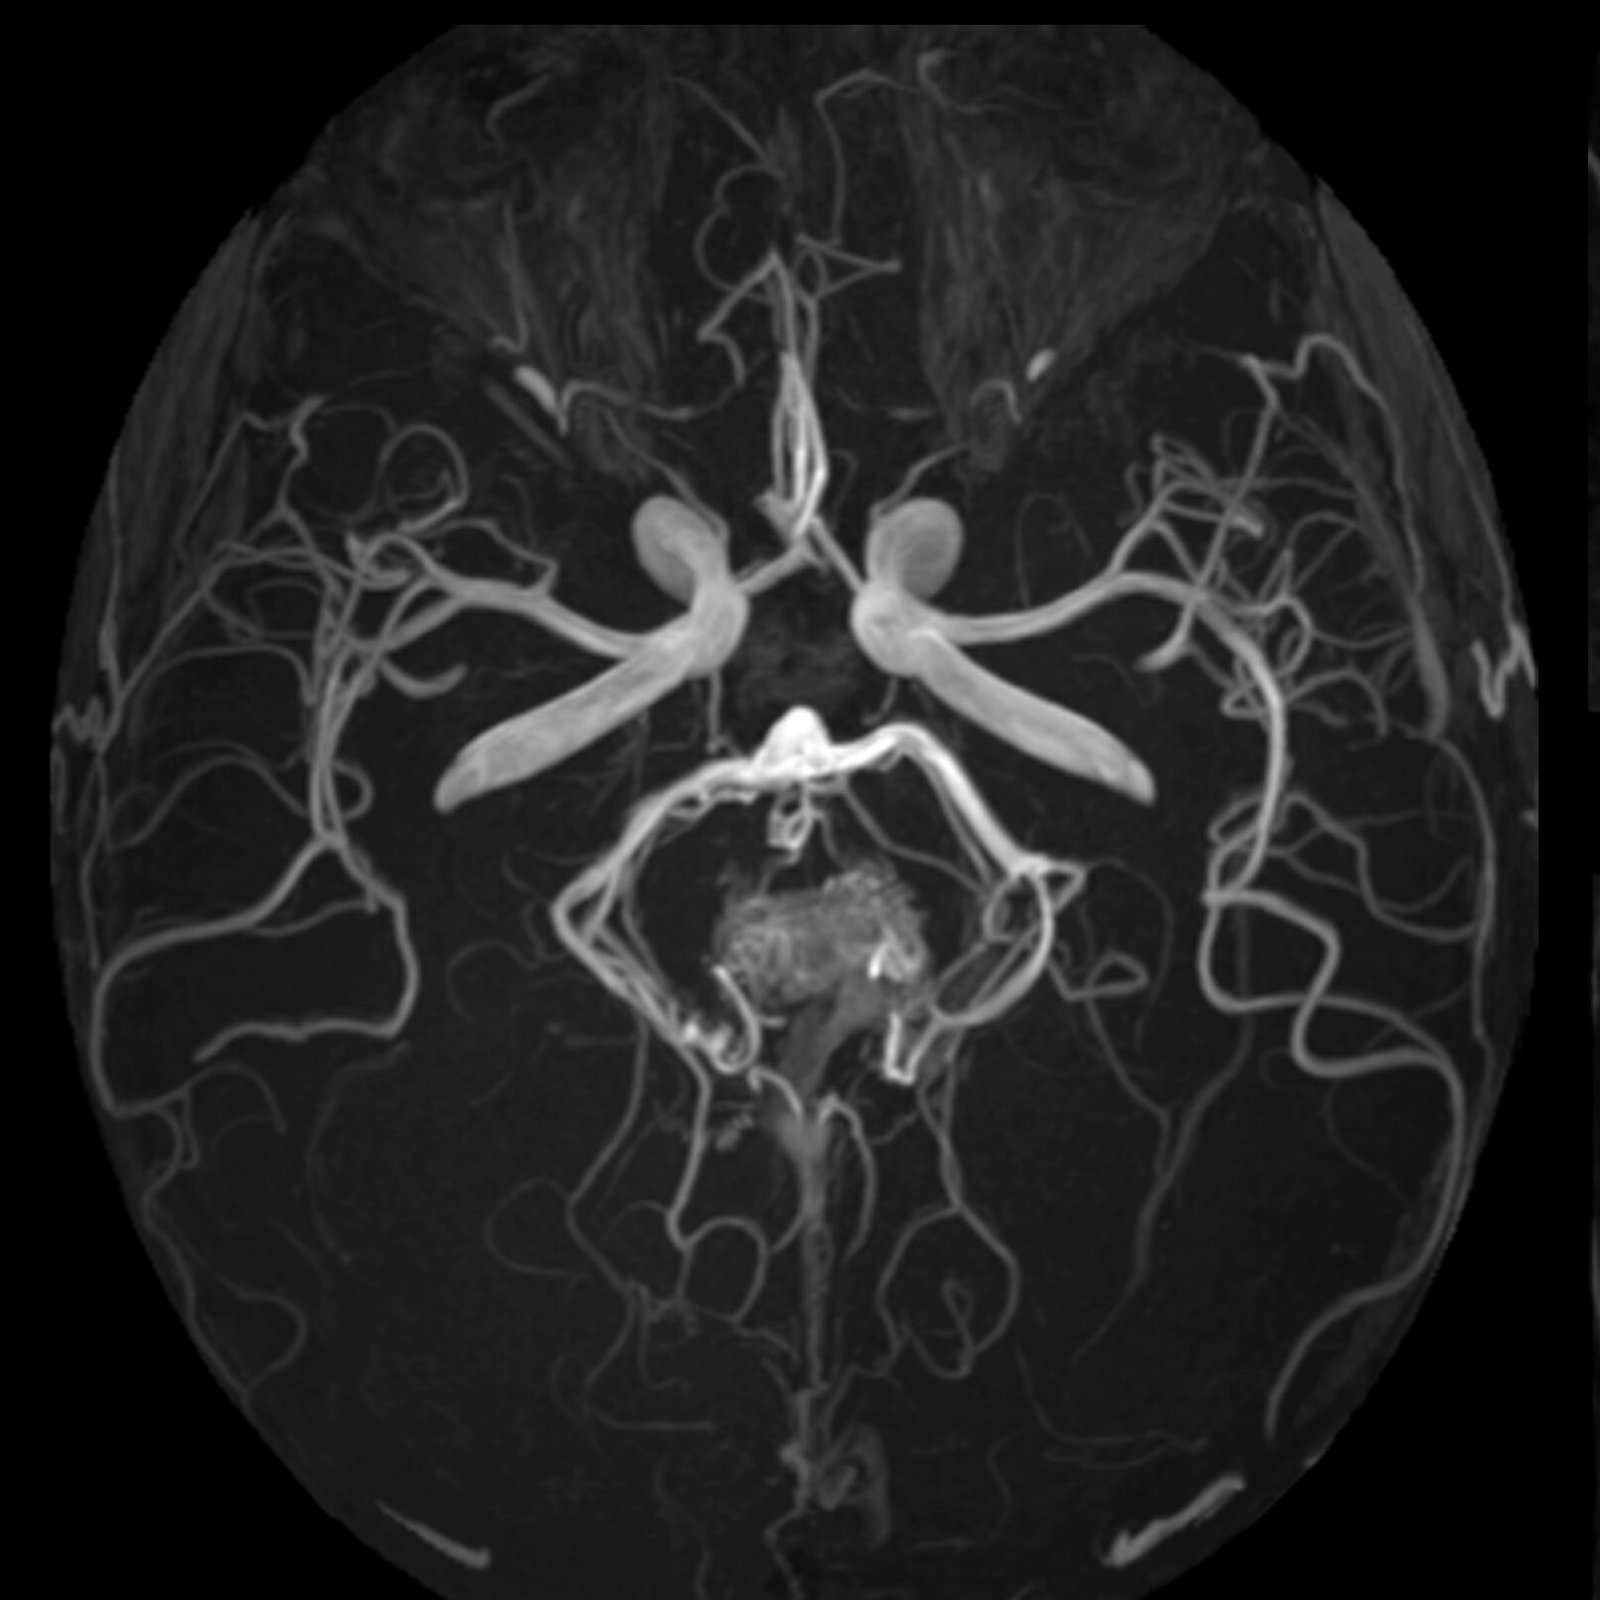

Neurovascular